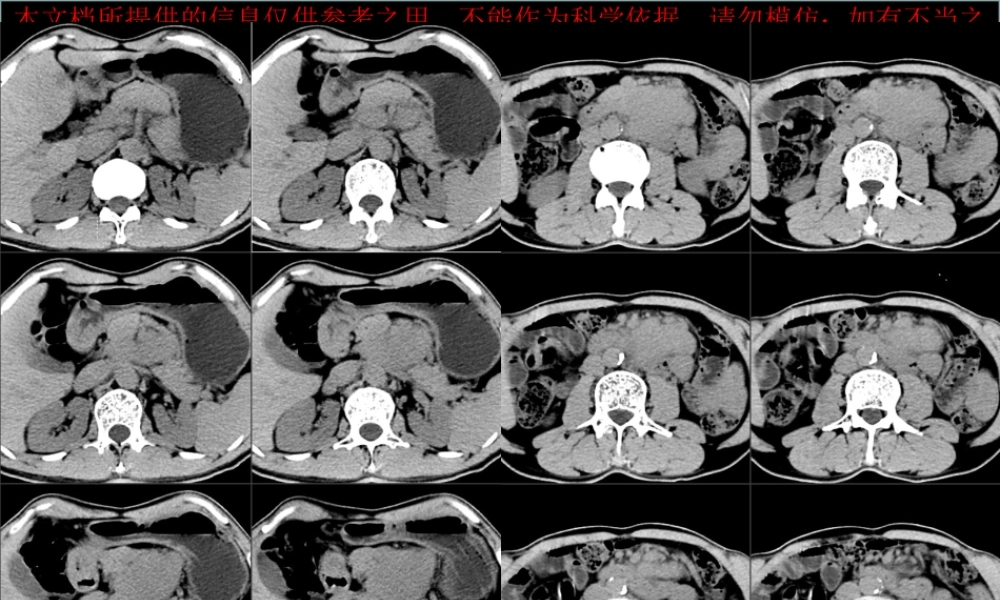

本文档所提供的信息仅供参考之用,不能作为科学依据,请勿模仿;如有不当之处,请联系网站或本人删除。本文档所提供的信息仅供参考之用,不能作为科学依据,请勿模仿;如有不当之处,请联系网站或本人删除。本文档所提供的信息仅供参考之用,不能作为科学依据,请勿模仿;如有不当之处,请联系网站或本人删除。本文档所提供的信息仅供参考之用,不能作为科学依据,请勿模仿;如有不当之处,请联系网站或本人删除。本文档所提供的信息仅供参考之用,不能作为科学依据,请勿模仿;如有不当之处,请联系网站或本人删除。病例 2本文档所提供的信息仅供参考之用,不能作为科学依据,请勿模仿;如有不当之处,请联系网站或本人删除。本文档所提供的信息仅供参考之用,不能作为科学依据,请勿模仿;如有不当之处,请联系网站或本人删除。本文档所提供的信息仅供参考之用,不能作为科学依据,请勿模仿;如有不当之处,请联系网站或本人删除。本文档所提供的信息仅供参考之用,不能作为科学依据,请勿模仿;如有不当之处,请联系网站或本人删除。病例 3本文档所提供的信息仅供参考之用,不能作为科学依据,请勿模仿;如有不当之处,请联系网站或本人删除。本文档所提供的信息仅供参考之用,不能作为科学依据,请勿模仿;如有不当之处,请联系网站或本人删除。本文档所提供的信息仅供参考之用,不能作为科学依据,请勿模仿;如有不当之处,请联系网站或本人删除。本文档所提供的信息仅供参考之用,不能作为科学依据,请勿模仿;如有不当之处,请联系网站或本人删除。Castleman 病CT 表现小讲座 福建医科大学附属第一医院影像科孙辉红( sunhvhong@sina.com )本文档所提供的信息仅供参考之用,不能作为科学依据,请勿模仿;如有不当之处,请联系网站或本人删除。病例 1•男, 58 岁,反复左上腹胀痛半年余。肿瘤标志物正常•*1 甲胎蛋白 (AFP) 1.580 0-13.6 ng/ml 电化学发光法 •*2 癌胚抗原 (CEA) 2.1 0-5.2( 吸烟者 :0-6.5) ng/ml 电化学发光法 •3 糖类抗原 125(CA125) 5.760 0-35 U/ml 电化学发光法 •4 糖类抗原 15-3(CA15-3) 10.230 0-25 U/ml 电化学发光法 •5 糖类抗原 19-9(CA19-9) 1.420 0-34 U/ml 电化学发光法 •6 糖类抗原 72-4(CA72-4) •淀粉酶 (AMYL) >35632 bg 32-641 U/L 干化学 强生 本文档所提供的信息仅供参考之用,不能作为科学依据,请勿模仿;如有不当之处,请...